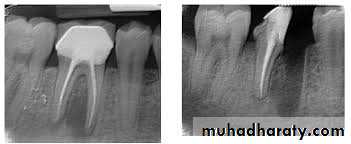

Usually four Photographs can be taken during An Endodontic procedures>

• Initial RadiographDiagnostic

2. Working length Radiograph

Used to determine the length of the canal

3.Final instrumentation radiograph(Master Cone)

Taken with the final size file /files/

4.Final radiograph (Root canal after Obturation)

Taken after the tooth has been temporized.

5. Recall Radiograph.

Taken at evaluation

Rdiographs in Endodontics

Show 4-5 mm beyond the apex of the tooth and the surrounding bone or pathologicPresent an accurate image of the tooth without elongation or fore-shortening

Exhibit good contrast so all pertinent structures are readily identifiable.

Requirments of Endodontic Films